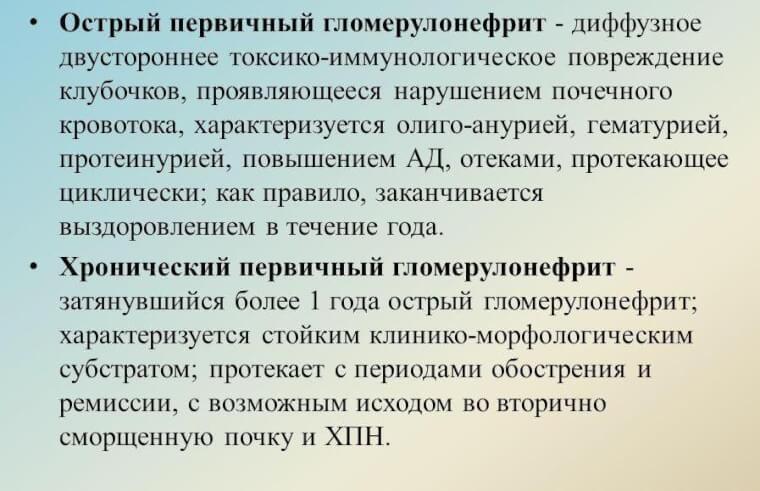

Механизм остро го диффузного гломерулонефрита